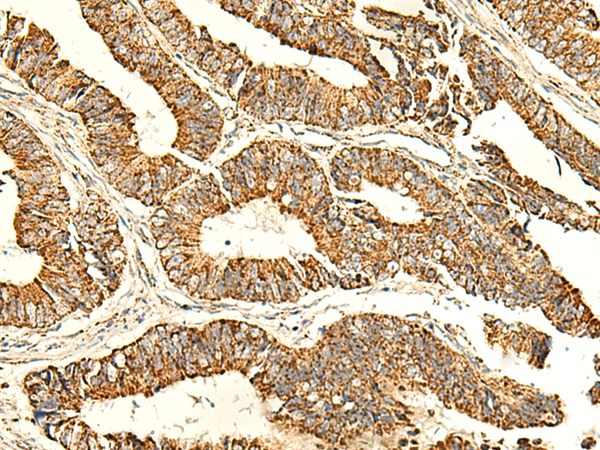

分类: 科研抗体货号: P10112别名: PUS4应用: IHC反应种属: Human, Mouse, Rat